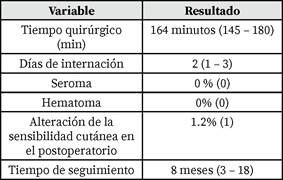

Resultados Quirúrgicos y Postoperatorios (Tabla 2)

El tiempo quirúrgico promedio fue de 164 minutos (145 - 180). El tiempo quirúrgico promedio reportado en la literatura para REPA o técnicas similares también se encuentra en estos rangos, por ejemplo, 99 min (85-124), Bayoux 2023(2), media 93.5 min (70-150), Coco 2022(12), media 146 min (76-221), Ferrara 2024(20), media 83 min, Juárez Muas 2019(3), media 164 min (150310), Mehta 2024(14), promedio 110 ± 10 minutos, Shinde 2022(15).

El tiempo de internación promedio fue de 2 días (1-3). Las estancias hospitalarias reportadas en otras series también son cortas: media 1.5 días, Bayoux et al 2023(2), media 2.3 días, Canton 2024(21), media 4 días, Köhler 2018(22), promedio 1.3 días, Juárez Muas 2019(3).

Durante el postoperatorio, no se registraron casos de seroma, hematoma o infección. La formación de seroma es la complicación más frecuente reportada en la literatura para la técnica REPA y similares, con incidencias que varían ampliamente, por ejemplo, 23%, Bayoux 2023(2), 12%, Juárez Muas 2019(3), 18.8%, Dong 2021(13), 15% en el primer mes, Kiudelis 2024(16). Los hematomas e infecciones son menos comunes, con tasas también variables. La ausencia de estas complicaciones en esta serie inicial de 12 pacientes es un hallazgo favorable.

Se presentó un caso (1,2%) de alteración de la sensibilidad de la piel abdominal. Las alteraciones de la sensibilidad cutánea (hipoestesia/parestesia) son efectos secundarios conocidos de los procedimientos en la pared abdominal que involucran disección subcutánea(6).

No se observó recurrencia de la diástasis ni de las hernias durante el período de seguimiento. Las tasas de recurrencia reportadas son generalmente bajas en las fuentes revisadas, variando entre 0% y 2.7% en la mayoría de las series (2).

El tiempo de seguimiento promedio de los pacientes fue de 8 meses (3 - 18). Los tiempos de seguimiento en la literatura también varían ampliamente, desde 2 meses hasta varios años(2),(20),(23).